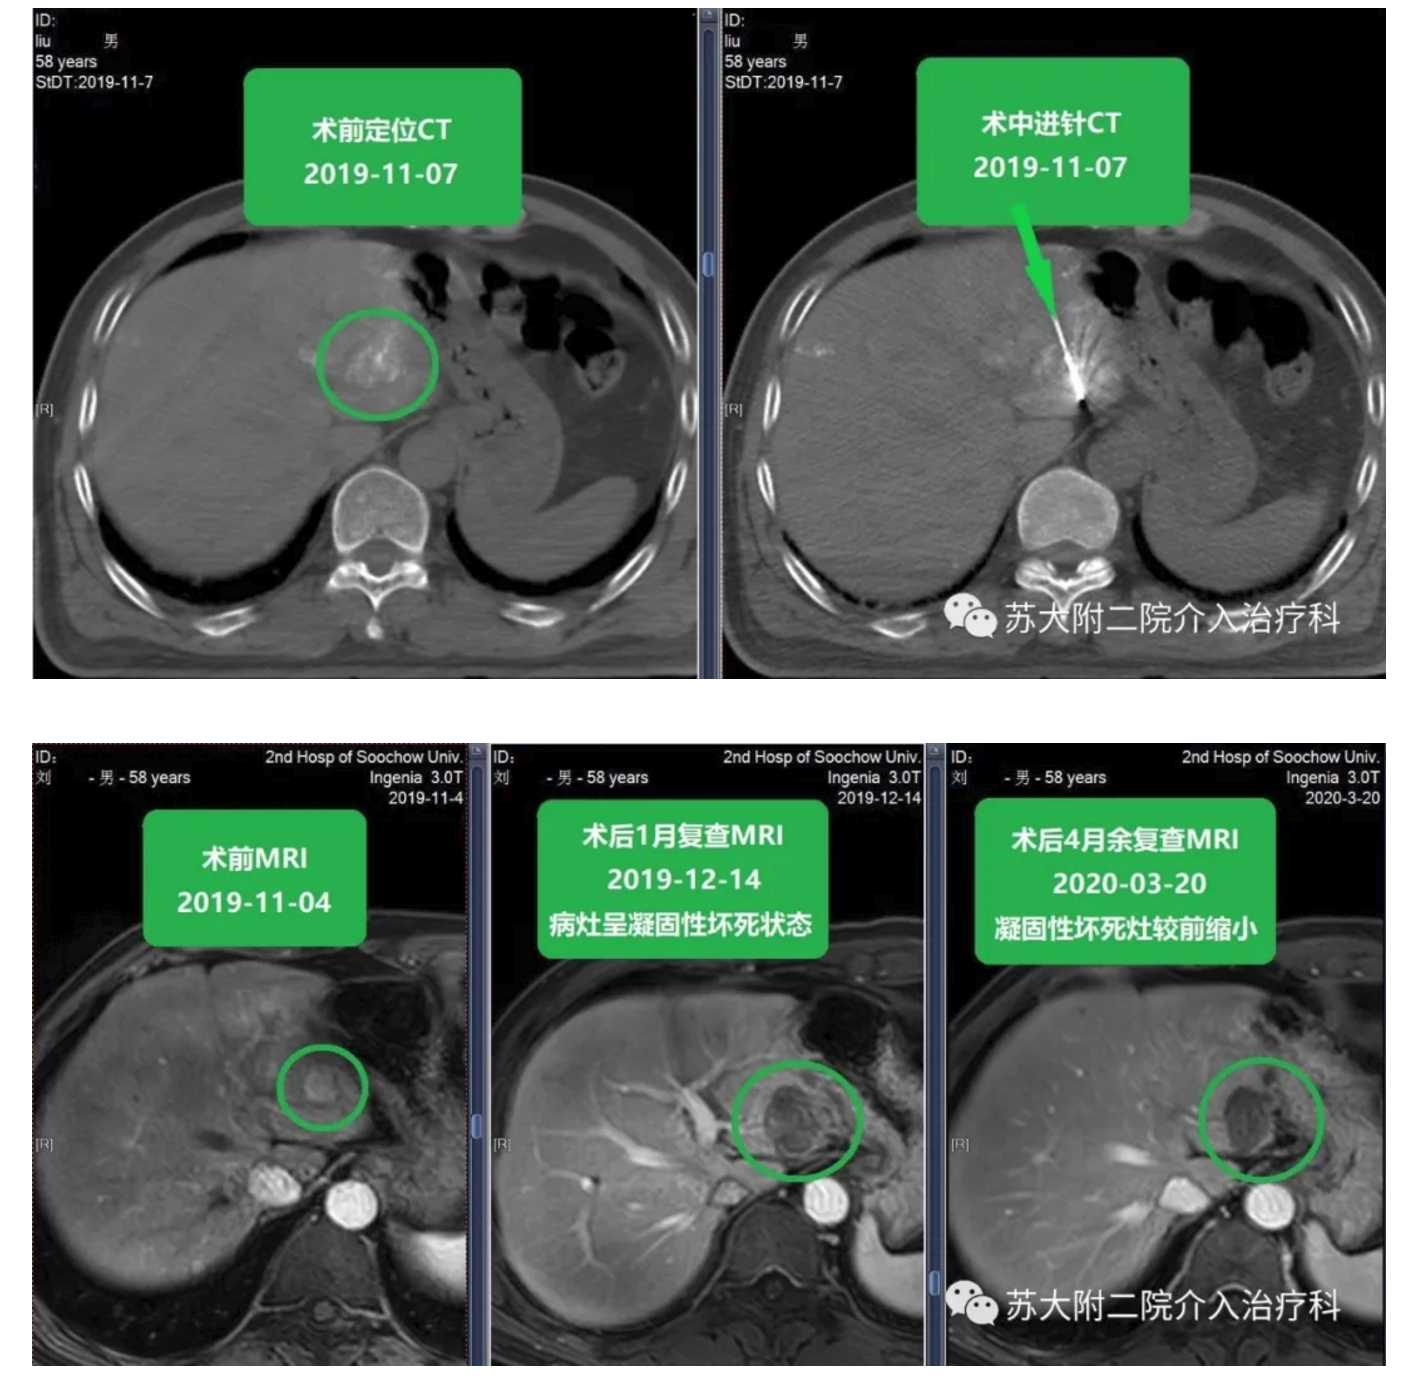

患者信息 刘**?? 男 ??58岁 简要病史 患者2016年7月行B超提示肝右叶占位,于2016-07-28行“腹腔镜下肝部分切除术+腹腔镜下胆囊切除术”,术后病理示:中分化肝细胞癌;术后口服索拉菲尼靶向治疗;2019-11-04复查MRI提示:肝左外叶异常信号灶,考虑HCC。既往:发现乙肝携带20年,2016年7月起口服药物治疗;2017年因痔疮行手术治疗。查体无异常。查血无异常。 入院诊断 肝癌术后复发 介入指征 患者拒绝外科手术切除。 治疗过程 2019-11-04腹部MRI提示肝左外叶异常信号灶,大小约1.7cm×1.4cm×1.3cm,于2019-11-06行TACE术,于2019-11-07行CT引导下肿瘤消融术,消融功率60W8min,术后无明显并发症。 随访复查 患者消融术后定期复查,病情稳定。 影像对比